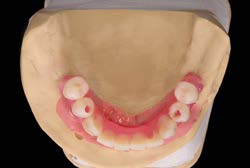

Các Implant ngắn 6.5mm BTI được đặt bằng cách sử dụng quy trình khoan định hướng sinh học (biologically guided drilling protocol) độc quyền của BTI, với lực vặn chèn được đo tại thời điểm đặt để xác nhận sự phù hợp cho việc chịu lực tức thì. Các phục hình tạm thời liên kết bắt vít được gắn ngay sau phẫu thuật để ổn định sự phân bố lực trong quá trình tích hợp xương. Từ 3 đến 6 tháng sau, chúng sẽ được thay thế bằng các cầu răng sứ kim loại cố định hoặc phục hình lai kim loại-nhựa, đảm bảo phục hình hoàn hảo cho bệnh nhân tiêu xương dọc.

Nghiên cứu cũng ghi nhận sự thay đổi rõ rệt ở bệnh nhân nữ muốn điều trị Implant vùng hàm dưới nhưng gặp hạn chế vì tiêu xương dọc quá lớn và hàm giả lỏng lẻo.